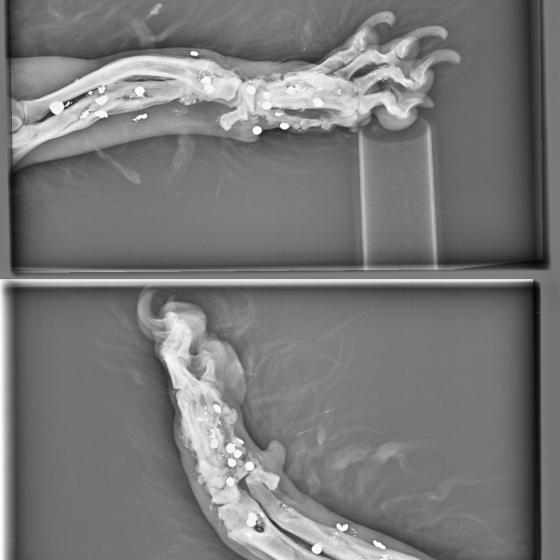

Brok, narodený marec 2019, sa našiel v obci Okoč. Krátko pred ním sa našiel veľmi podobný psík, do ktorého deti hádzali petardy. Brok žiaľ skončil horšie :( Celý je dostrieľaný, má v sebe kopu brokov, ktoré mu ale našťastie nevadia. Až na nožičku :( Tá je úplne dostieľaná, dolámaná a modlíme sa za zázrak, aby sa ešte dala zachrániť :( Brok ide na vyšetrenia, ktoré definitívne potvrdia či príde o nožičku, ale môže podstúpiť korekčné operácie, ktoré ale budú veľmi nákladné. Samozrejme do nového domova pôjde až po zákroku. Nožička ho našťastie vôbec nebolí, neprekáža mu, len trocha zavadzia, lebo ju nevie veľmi požívať :( Je to neskutočne tešívé, prítulné, veselé, spoločenské psíča, ktoré si hľadá aktívnu rodinu. Nie je vylúčené, že z neho bude trojnožka, ale na jeho povahe to nič nezmení :) Je znášanlivý, kontaktný, pozorný. Veľmi si užíva spoločnosť človeka, rád sa túli a mojká. Najspokojnejší je keď môže voľne behať vo výbehu. Na vodítku je trocha opatrný, ale to sa rýchlo doučí. Hľadáme mu rodinku, v ktorej bude plnohodnotným členom a nie ozdobou na záhrade. Je vhodný aj do bytu, ale bude treba doladiť prechádzky na vodítku a hygienické návyky. Ak ba sa mal adoptovať k rodinnému domu, tak výhradne s celoročným prístupom k svojej rodine. Brok čaká na svoju druhú šancu od marca 2020.